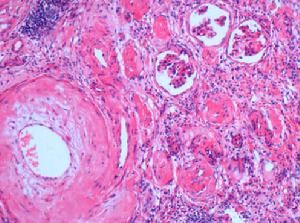

腎萎縮--切片腎萎縮治療進展

各類腎病發展到腎衰竭、尿毒症後,腎臟也隨之萎縮,在腎病臨床領域對於腎萎縮治療一直持有悲觀情緒,認為腎萎縮治療無任何好的方法,只能慢慢拖延直至腎臟功能全部喪失以腎移植來維持生命。但隨著中國腎病醫療事業的發展,腎病學術界對於腎萎縮治療前景也逐漸樂觀。腎萎縮治療治病要尋根

要找到有效治療腎萎縮的方法,需要探究腎萎縮產生的根本性原因。腎臟受到外界的侵襲,炎症反應發生、細胞表型轉化導致腎臟纖維化的逐漸發生與進展,從而腎臟實質受到損害,腎臟也隨之縮小。而對腎萎縮治療也應該把治療重點放在如何阻止腎臟纖維化上,這一觀點的確立與腎病年會的精神不謀而合。隨著腎臟纖維化理論被普遍接受,石家莊腎病醫院治療腎萎縮的方法也被更多的專家所支持並推崇。腎臟纖維

腎臟纖維

減少ECM的合成增加其降解作用,腎臟受損組織就還有可能得以部分修復,腎功能也可以逐漸的恢復,肌成纖維細胞和免疫複合物的凋亡,阻斷其繼續合成和分泌增ECM,增加腎臟內降解酶的生成,增強其對ECM的降解活性,減少ECM對腎臟組織的破壞,逐漸逆轉受損的腎臟功能。